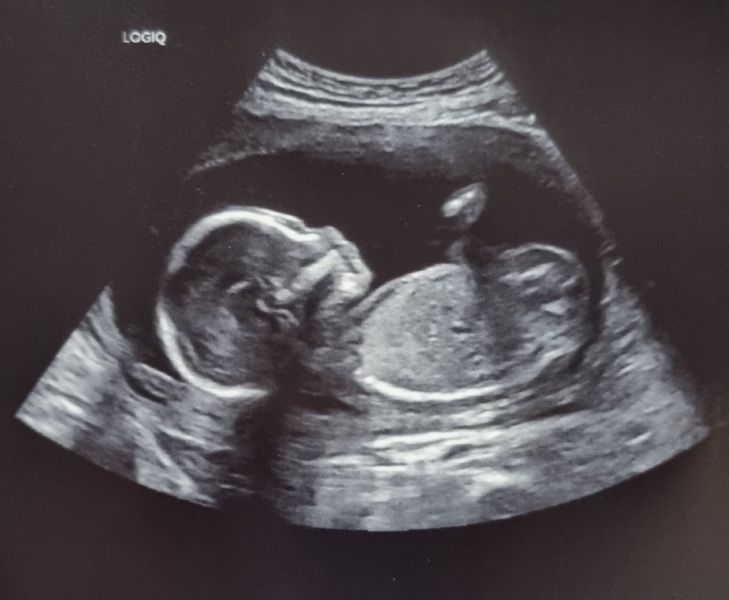

ChristmasJumpers · 12/11/2022 11:12

So so lovely to hear about all the 20 week scans. We never got told the percentile and forgot to ask! Picture of our girl at exactly 20 weeks on Thursday 🥰

Due March 2023 - thread 4